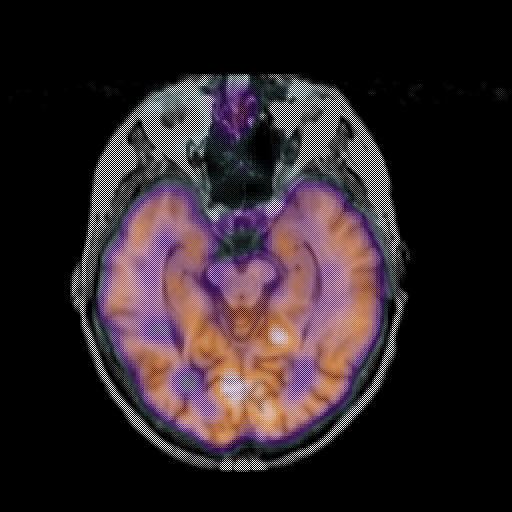

overlay: Slice 21

Slice 21

MRCBFCBF with

T1PDT2T1PDT2